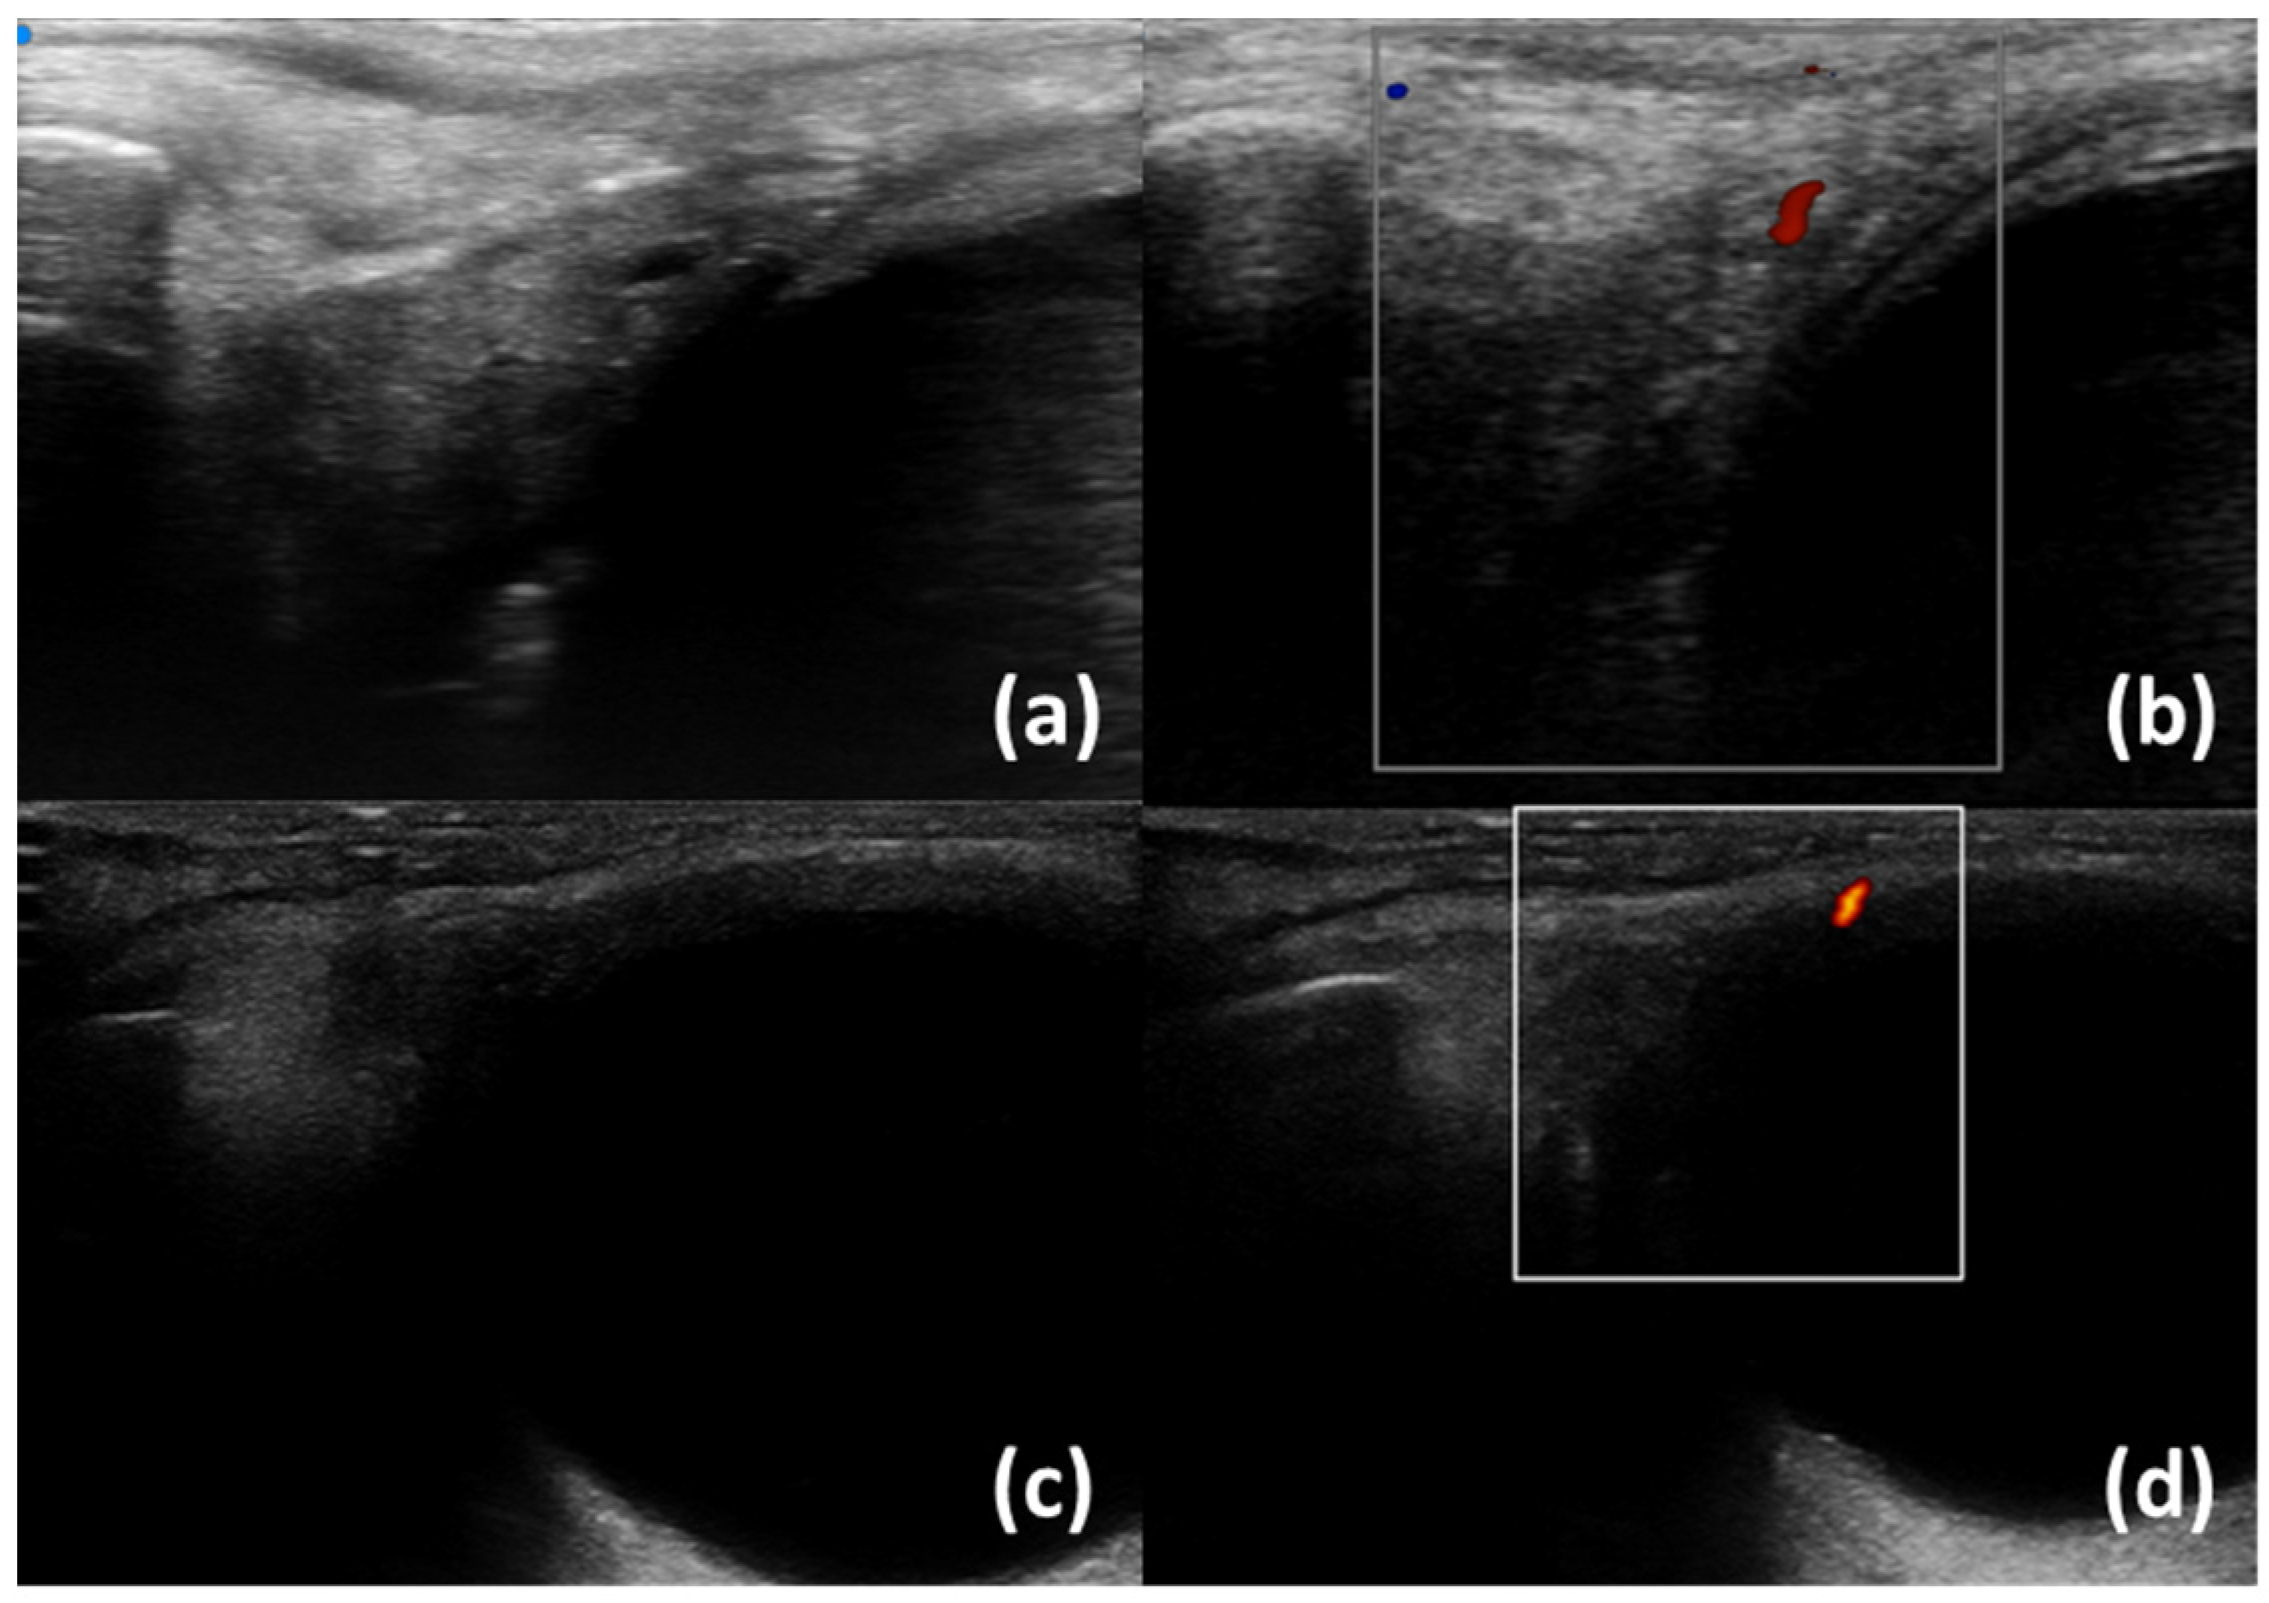

| Ferro et al. (2020) [35] | B-mode | SjD diagnostic value (SjD patients have higher inhomogeneity) Associations of inhomogeneity with Ro/SSA+ positivity Correlationsof inhomogenity with histological inflammation |

| Izzetti et al. (2021) [20] | B-mode | Support to the biopsy procedure |

- Ferro, F.; Izzetti, R.; Vitali, S.; Aringhieri, G.; Fonzetti, S.; Donati, V.; Dini, V.; Mosca, M.; Gabriele, M.; Caramella, D.; et al. Ultra-high frequency ultrasonography of labial glands is a highly sensitive tool for the diagnosis of Sjögren’s syndrome: A preliminary study. Clin. Exp. Rheumatol. 2020, 38 (Suppl. S126), 210–215. [Google Scholar]

- Fulvio, G.; Ferro, F.; Izzetti, R.; Governato, G.; Fonzetti, S.; La Rocca, G.; García, I.C.N.; Donati, V.; Mosca, M.; Baldini, C. POS1461 advantages of doppler in labial salivary gland ultra-high frequency ultrasound: Correlations with histological inflammation, pSS diagnosis, disease activity, and prognosis. Ann. Rheum. Dis. 2023, 82 (Suppl. S1), 1085. [Google Scholar] [CrossRef]